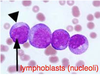

What are the molecular and morphologic changes of the image? ( MDx)

Clinical history and signs: 3 week old puppy, anorexia, dypsnea, abd pain upon palpation, normal rectal temperature

Multifocal, acute renal necrosis and hemorrhage or necrohemorrhagic nephritis

What is the etiology?

Clinical history and signs: 3 week old puppy, anorexia, dypsnea, abd pain upon palpation, normal rectal temperature

Canine herpesvirus-1 (CHV-1)

- red spots are from the virus targeting endothelium

What is the pathogenesis?

Clinical history and signs: 3 week old puppy, anorexia, dypsnea, abd pain upon palpation, normal rectal temperature

Transmission CHV-1 to pup at birth >incubation period of up to 1 week > virus replicates at temperature lower than 37C (98.6F) > endothelial cell tropism > multifocal necrosis in numerous organs